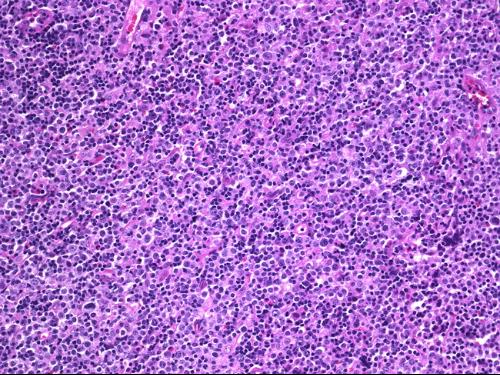

T-淋巴细胞